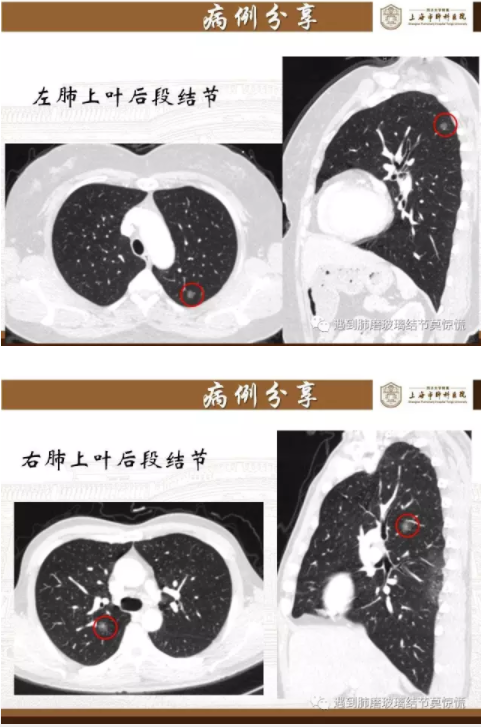

下面就我们的病例分析一下怎么进行肺段切除。

MIA= 微浸润腺癌   IA= 浸润性腺癌   AIS= 原位腺癌   AAH= 不典型腺瘤样增生